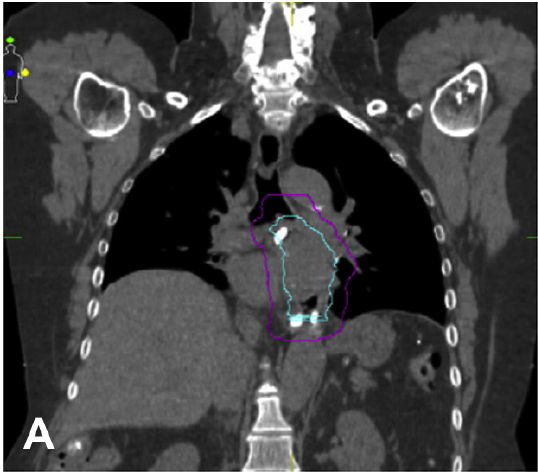

The CUPID study aims to increase the understanding of the relationship between paediatric IBD and cardiovascular risk, facilitating the development of preventative strategies and identification of populations who would benefit most. The CUPID is assessing intermediate cardiovascular phenotypes – non-invasive measures of arterial structure and function that are thought to predict later cardiovascular risk and disease. This study involves close collaboration between the Gastroenterology Department, Royal Children’s Hospital, Melbourne and the Infection and Immunity Group, Murdoch Children’s Research Institute.

CUPID is a cross-sectional case-control study investigating the cardiovascular intermediate phenotypes of children with established IBD, including non-invasive macro- and micro-vascular assessment, and biomarkers of inflammation and adverse cardiovascular status. It is, as far as we are aware, the most detailed cardiovascular assessment of children with IBD to date. The study is aiming for 80 patients with Crohn’s disease or ulcerative colitis of at least six months duration aged 7-18 years, and 80 age-and sex matched controls.

The study currently has 66 children with IBD and 66 healthy comparison participants. Each of the 66 IBD patients and 66 comparison participants have had fasting plasma glucose, lipid profile, high sensitivity C-reactive protein, carotid-femoral pulse wave velocity (PWV), carotid intima-media thickness (cIMT), abdominal aorta intima-media thickness (aIMT), and retinal vascular calibre performed. Recruitment is nearing completion and analysis of the above measures has commenced.